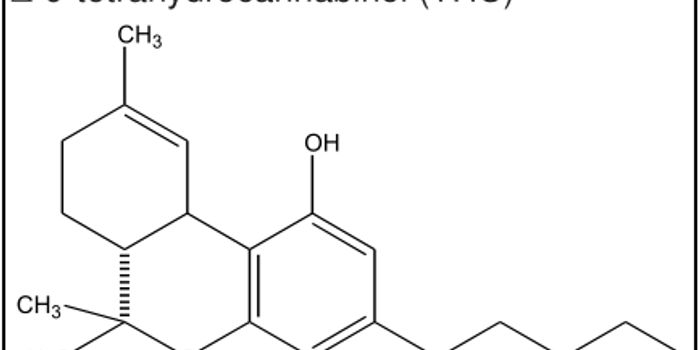

NOV 26, 2019Cannabis SciencesInnovative technology allowed researchers to conduct the first-ever study of cannabis use for the treatment of headache ...

AUG 28, 2021Cannabis SciencesEye-tracking data shows promise for detecting levels of tetrahydrocannabinol (THC). The corresponding study was publishe ...

FEB 03, 2022Cannabis SciencesA primary limitation of cannabis research thus far has been the inconsistent quantification of exposure to the plant&rsq ...